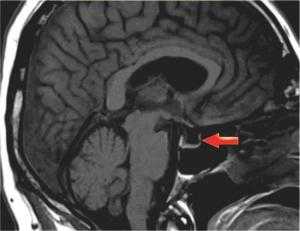

При ретроспективном анализе МРТ головного мозга пациента № 1 с контрастным усилением выявлено увеличение поперечного и вертикального размера гипофиза, утолщение воронки, потеря дифференцировки между адено- и нейрогипофизом и отсутствие характерного гиперинтенсивного сигнала Т1-взвешенного изображения (ВИ) от нейрогипофиза. Верхний полюс увеличенного гипофиза компримировал хиазмальную цистерну и хиазму. Измененный гипофиз имел среднеинтенсивный сигнал на Т2-ВИ и Т1-ВИ. В правой половине выявлялась локальная зона отека. После введения контраста отмечалось интенсивное гомогенное усиление от всего гипофиза и накопление утолщенными менингеальными оболочками контраста в виде «усиков» по скату основной кости (рис. 4).

Рис. 4. Больной № 1. Т2-ВИ гипофиза в аксиальной (а) и фронтальной (б) плоскости. Железа увеличена в размерах в параселлярном и супраселлярном направлениях, Утолщена воронка (обозначена кружком). На фоне среднеинтенсивного сигнала выявляется локальная зона отека (обозначена стрелкой). Сифоны внутренней сонной артерии интактны. Т1-ВИ гипофиза во фронтальной плоскости до (в) и после (г) внутривенного контрастного усиления. Сигнал от пораженной железы достаточно гомогенный, среднеинтенсивный. Отмечается интенсивное гомогенное контрастирование ткани гипофиза. Сифоны внутренней сонной артерии интактны. Т1-ВИ в сагиттальной плоскости до (д) и после (е) внутривенного контрастирования. До контрастирования визуализируются выраженный супраселлярный тип роста железы, отсутствие типичного высокоинтенсивного сигнала от нейрогипофиза (указано стрелкой). На постконтрастном изображении отмечается равномерное контрастное усиление железой и наличие контрастного усиления по утолщенной менингеальной оболочке вдоль ската основной кости (указаны желтыми стрелками), а также контрастированные менингеальные «усики» (указаны красными стрелками) или феномен «dural tail».